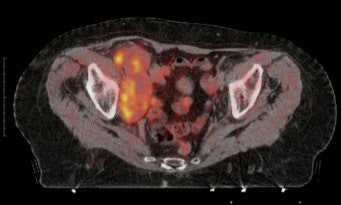

Example of the use of new radiopharmaceuticals: 11C-choline imaging of pathologic lymph nodes in advanced bladder cancer. Bulky disease in the right iliac region is easily recognized on PET/CT.Traditional nuclear medicine techniques -- the first tools to image molecular changes in the living body -- are evolving slowly compared with PET, and are considered mature imaging modalities, with well-defined diagnostic accuracy. FDG-PET, the well-known glucose analogue, is also considered a reliable tool for many applications: entering "FDG PET" into PubMed brings more than 40,000 items between 1975 and 2011. Thanks to FDG, many centers are already settled throughout the world and many others are on the way.